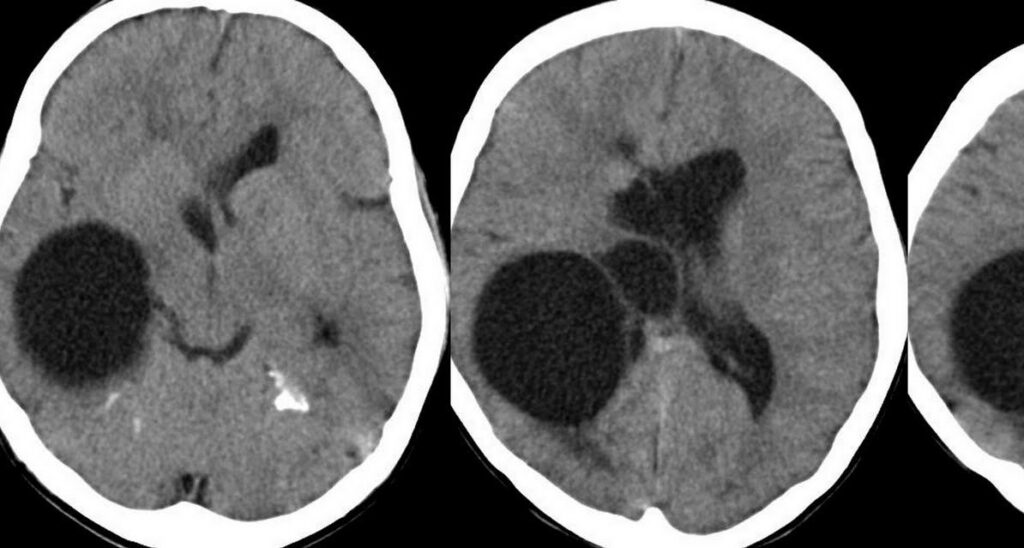

Porencefalia

Porencefalia é uma doença extremamente rara que acomete o sistema nervoso central. Surgem cistos e cavidades em um hemisfério cerebral podendo acontecer antes ou depois do nascimento.

Os cistos são em geral resultado de destruição tecidual por infecção ou doença vascular.